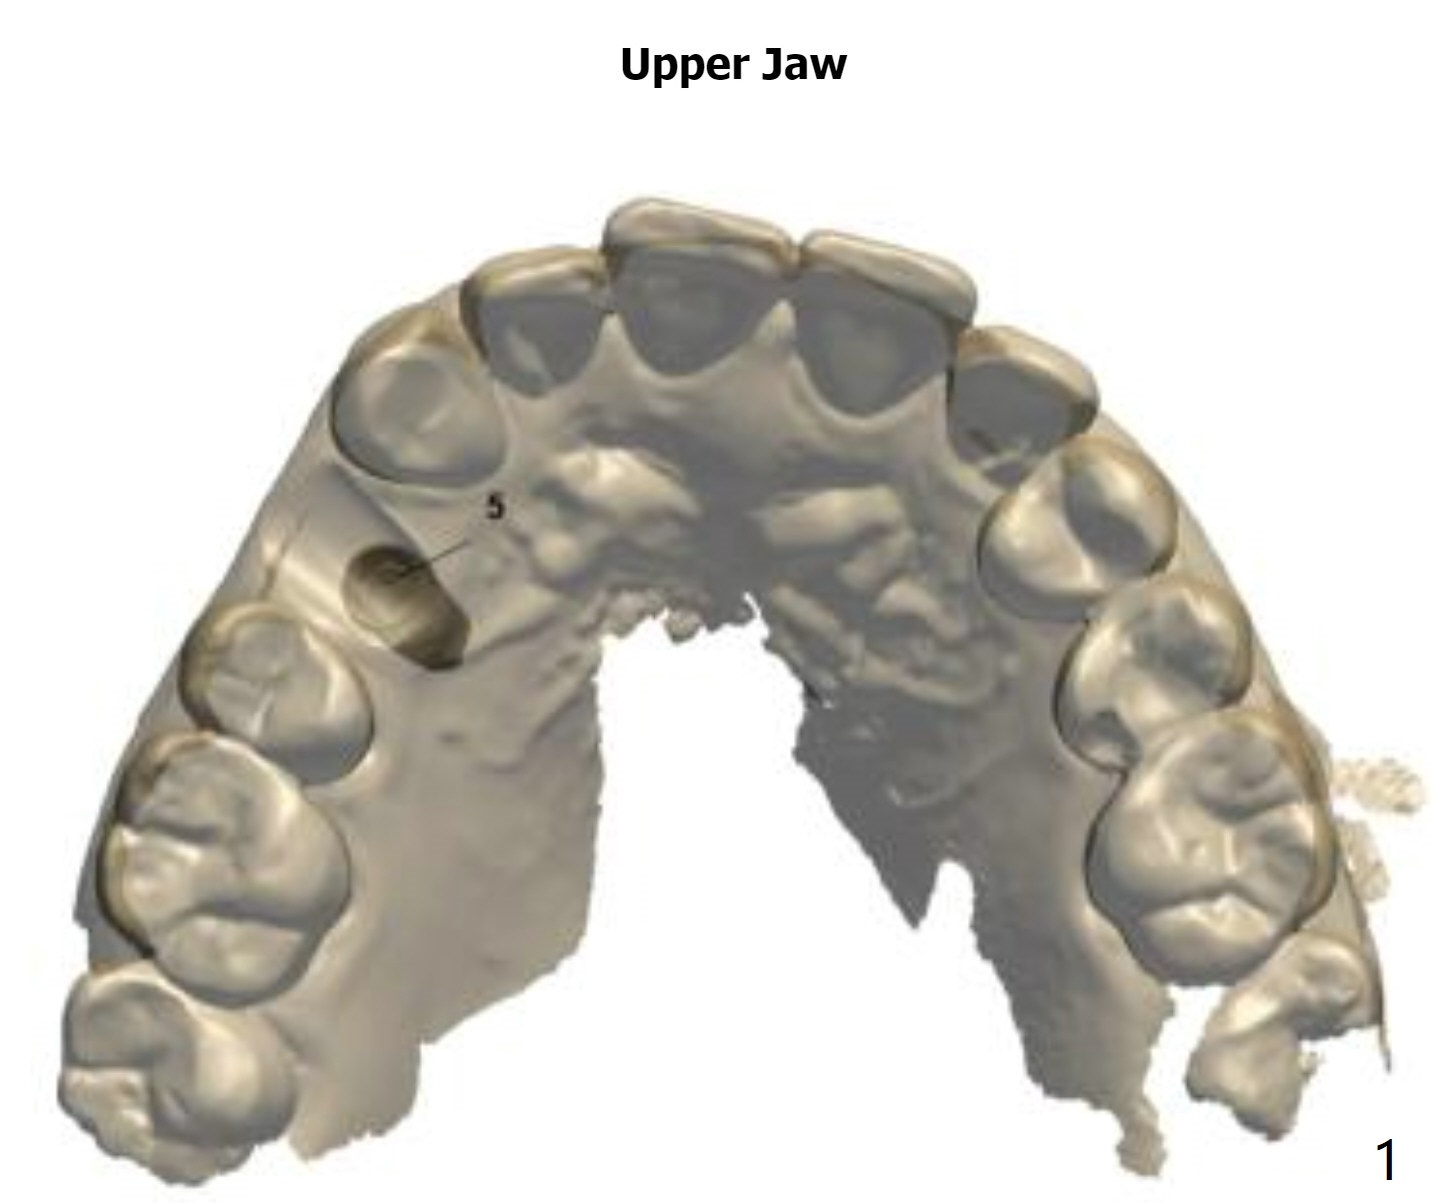

A 46-year-old woman

Xin Wei, DDS, PhD, MS 1st edition 06/28/2021, last revision 07/24/2021